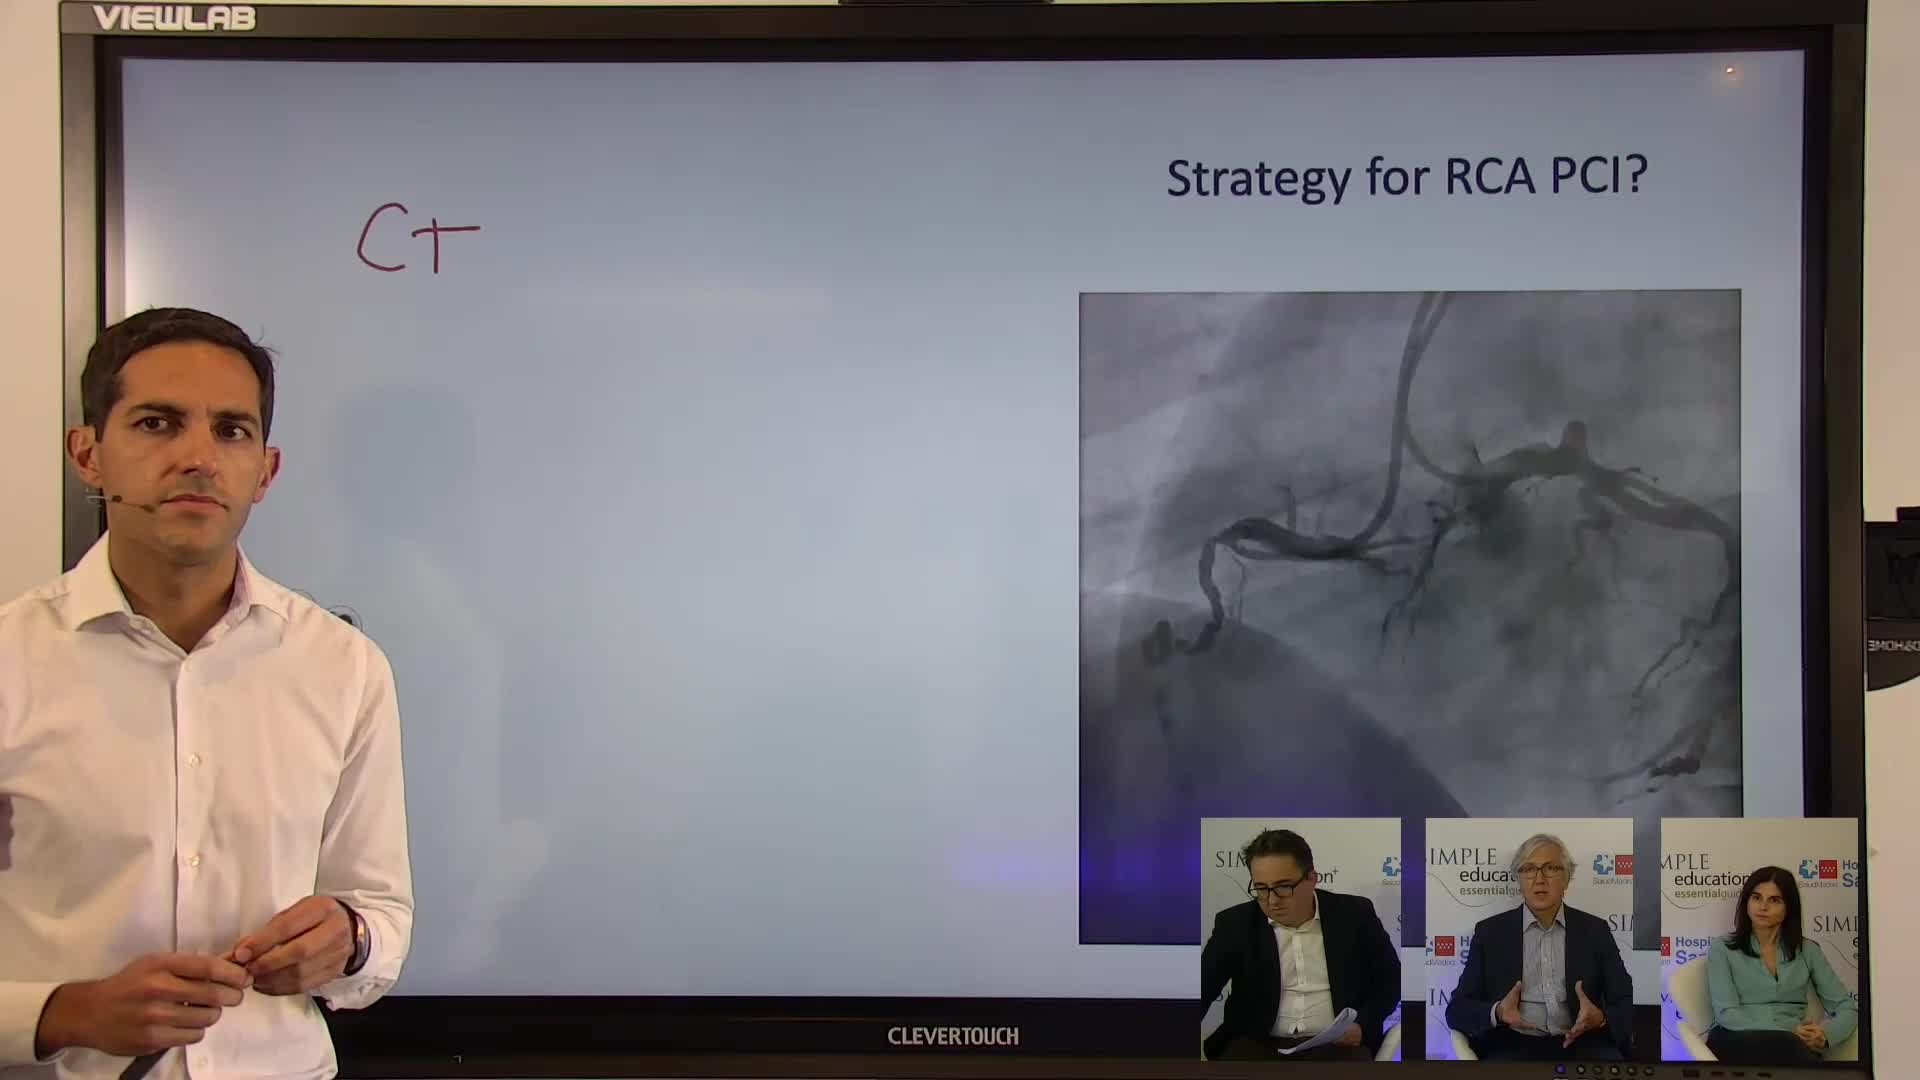

Best practices and personalised medicine in complex PCI - Prof Javier Escaned

Essential steps for physiology-based PCI planning and guidance - Dr Allen Jeremias

Coronary Bifurcations: An Update on Diagnosis, PCI planning and Imaging and PhysiologyGuidance - Dr Dejan Milasinovic